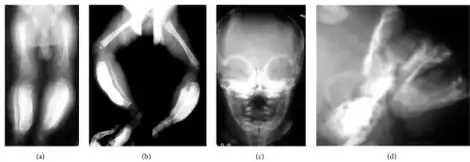

| a,b) Massive cortical thickening/bowing both tibias are shown c,d) massive external cortical of mandible in frontal/lateral projection | |

Radiographs initially show layers of periosteal new bone formation with cortical thickening. Periosteal new bone may cover the diaphysis of the bone, causing an increase in diameter of the bone. Over time, the periosteal new bone density increases, becoming homogenous with the underlying cortex. Eventually, the bone remodels and resumes a normal appearance.